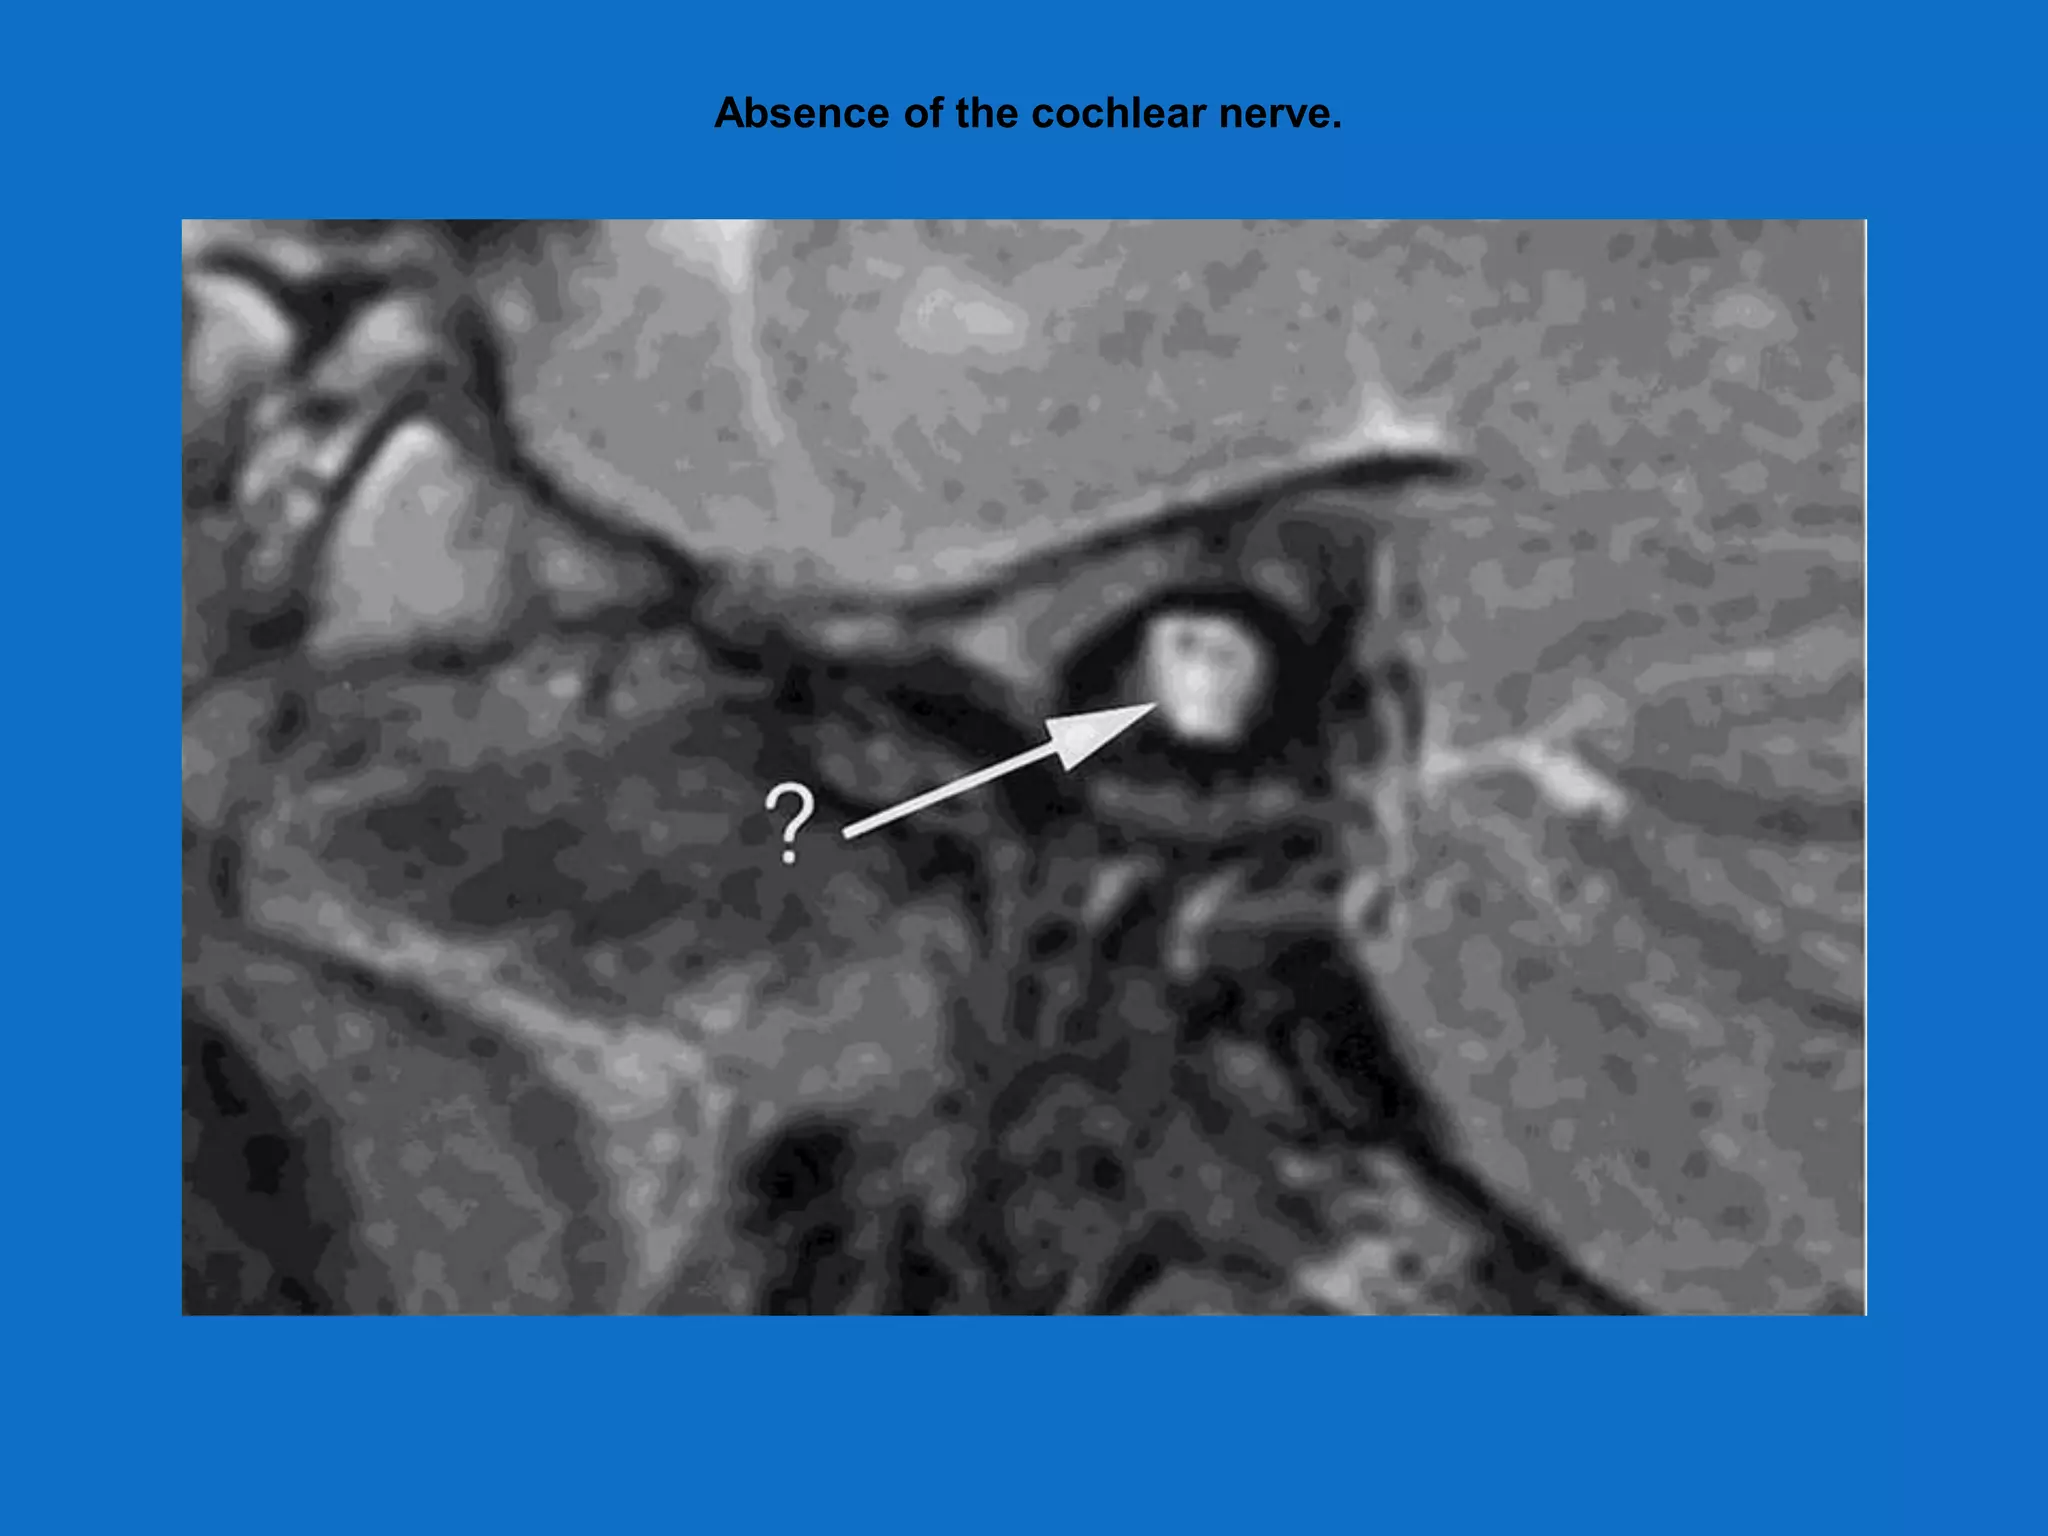

Radiology absolute requirements

• Presence of cochlea(either normal or

malformed)

• Presence of auditory nerve

• Combination of CT/MRI is performed

Cochlear aplasia.

Absence of the cochlear nerve.

Radiology absolute requirements •Presence of cochlea(either normal or malformed) • Presence of auditory nerve • Combination of CT/MRI is performed

Absence of thecochlear nerve.